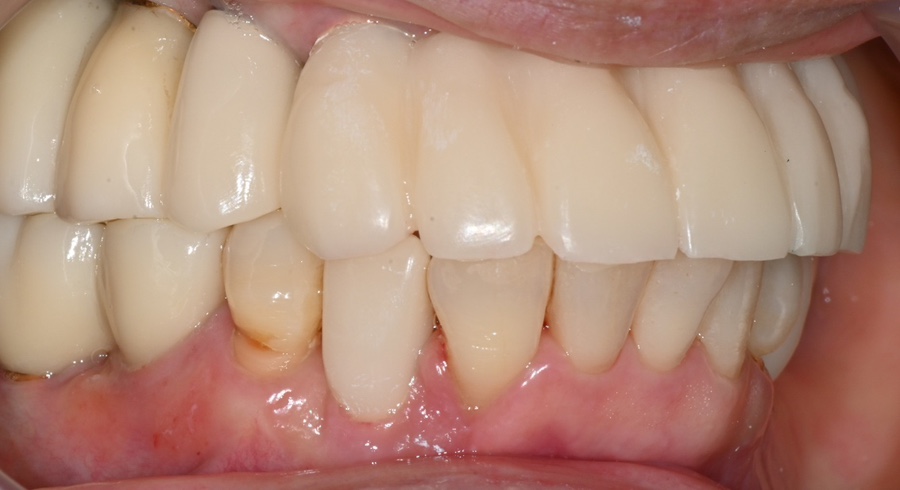

Final zirconia prosthesis placement

After sufficient adjustment,

we placed the final zirconia prosthesis.

It was designed to flow naturally from the front tooth line to the molar line,

and

we carefully adjusted the bite so that chewing force would not be concentrated on one side.

3-month check after placement

Full-mouth implant surgery

When the patient returned 3 months later,

the implants, prostheses, and gums were all in a stable condition.

There was a feeling that the left side was chewing a little less,

so we made a very slight adjustment to the occlusal surface,

and after that, the patient has been using them comfortably.